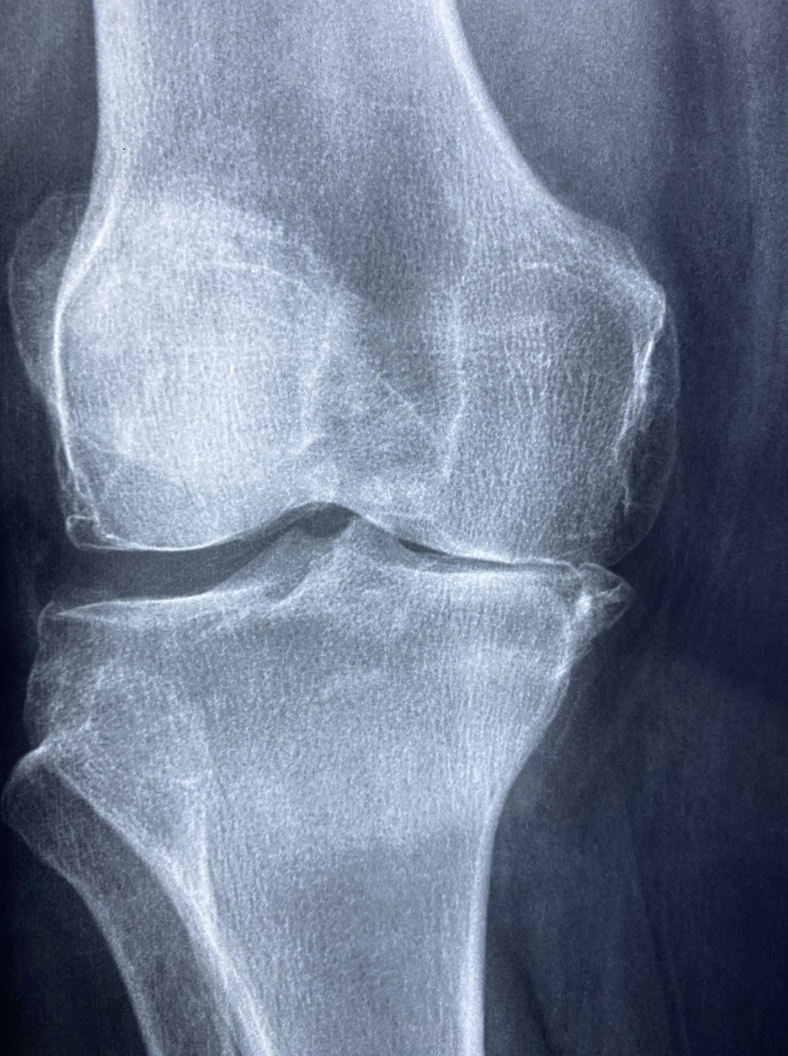

관절 통증은 보통 노화와 함께 오는 거라고 생각하지만, 요즘은 30~40대 젊은 층에서도 관절 이상을 호소하는 분들이 많아요. 스마트폰이나 컴퓨터 사용 시간이 길어지면서 손목, 목, 허리 관절에 무리가 가기 때문이죠. 그리고 운동을 잘못된 자세로 하거나, 무리한 다이어트를 반복하다 보면 연골이 점점 닳게 돼요. 제 경우엔 등산 갔다가 무릎을 삐끗한 이후로 유난히 계단이 힘들더라구요. 관절은 한 번 손상되면 회복이 어렵기 때문에 미리미리 챙기는 게 정말 중요합니다.